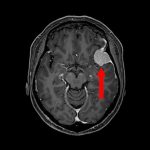

676

'25年10月

20代

脳幹部腫瘍

頭蓋内腫瘍摘出術